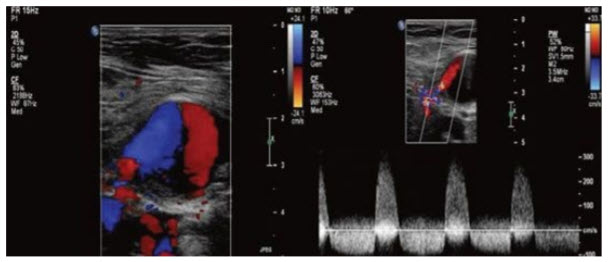

During rounds in the telemetry unit you evaluate a 55-year-old woman 1 day after she underwent a left heart catheterization. She complains of right groin pain and swelling at the vascular access site. You order a duplex ultrasound of the right groin. Findings of the ultrasound are illustrated in Figure below A and B.

What is your diagnosis?

Pseudoaneurysm. The spectral Doppler waveform shown is a typical toand-fro signal seen within the neck of the pseudoaneurysm. The incidence of pseudoaneurysm complicating percutaneous arterial procedures ranges between 0.2% and 0.5%. Patients typically present post catheter-based procedure with a painful pulsatile mass. When small these may resolve spontaneously, while others require intervention such as ultrasound-guided thrombin injection or surgical repair.